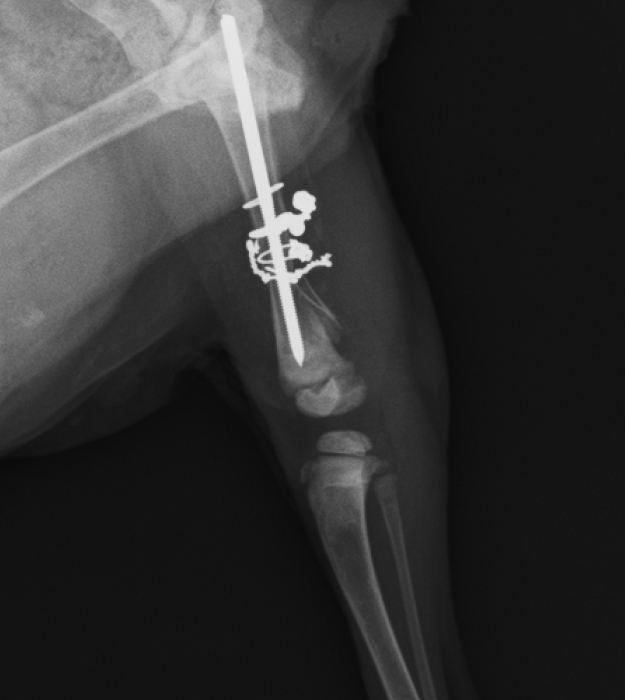

レントゲンにあるように

複雑な骨折になっており、細かい骨も周りに散らばり

靭帯が損傷し膝の可動域が現在ない状態で曲がらない。

という状態でした。

まずはレントゲンの写真をご覧ください

6月17日でのレントゲンです

固着してきてますが、骨の欠片が飛び出ているようになっています。

そして抜糸当日の24日

完全に固着していないものの、飛び出した骨も安定してきており

先生の判断で抜糸という経緯になりました。

治療・手術対象

ミント(猫、雑種、2か月、メス)

治療・手術内容

右後ろ脚の複雑骨折及び靭帯損傷